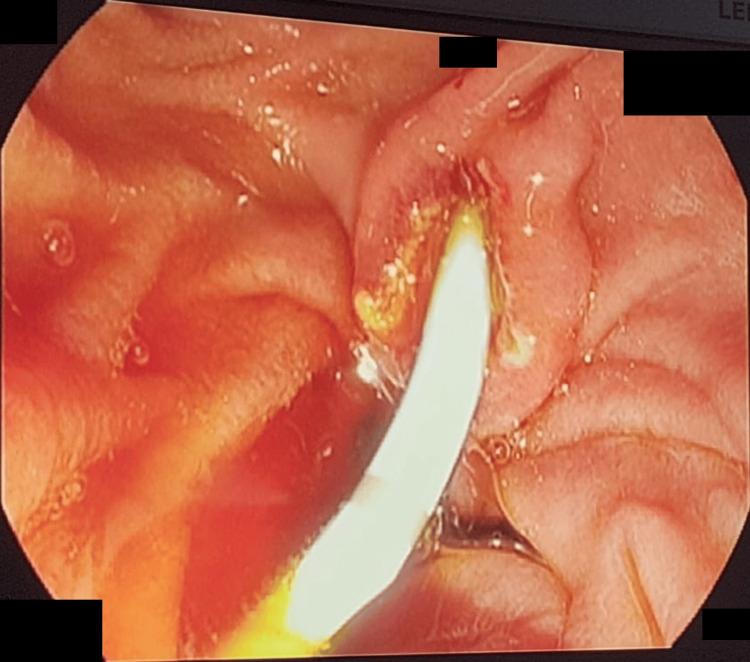

A contracted or "vanishing" gallbladder is a condition characterized by severe atrophy or fibrosis of the gallbladder, often resulting from chronic inflammation, recurrent cholecystitis, gallstone disease, or metabolic disorders such as diabetes and chronic alcohol use. The etiopathogenesis involves progressive fibrosis due to persistent biliary obstruction, chronic infection, or impaired blood flow, particularly in patients with liver cirrhosis. While the exact incidence remains unclear, it is more prevalent in individuals with long-standing hepatobiliary diseases or metabolic syndromes. Common symptoms include severe right upper quadrant pain, jaundice, nausea, vomiting, and signs of obstructive jaundice, such as dark urine and pale stools. Diagnostic investigations typically involve ultrasound, contrast-enhanced computed tomography (CECT), magnetic resonance cholangiopancreatography (MRCP), and endoscopic retrograde cholangiopancreatography (ERCP) to assess biliary obstruction, liver pathology, and gallbladder morphology. Treatment requires a multidisciplinary approach, including initial ERCP for biliary decompression, followed by surgical intervention (laparoscopic or open cholecystectomy), with conversion to open surgery often necessary due to dense adhesions and fibrosis. Postoperative care focuses on managing comorbidities, preventing complications, and long-term monitoring of liver health. This case report presents the challenging management of a 34-year-old male with a history of diabetes mellitus, chronic alcohol use, and liver cirrhosis, who presented with severe right upper quadrant pain, jaundice, and ascites. Initial evaluation revealed cholangitis, calculous cholecystitis with choledocholithiasis, and imaging findings consistent with liver cirrhosis. The patient underwent ERCP for biliary stenting and sludge extraction, followed by an attempted laparoscopic cholecystectomy. Intraoperatively, dense adhesions and fibrosis obscured the gallbladder, confirming a contracted or "vanishing" gallbladder, prompting conversion to an open procedure. The case highlights the diagnostic complexities of contracted gallbladders, which often result from chronic inflammation, fibrosis, or metabolic disorders. Preoperative imaging, including ultrasound and MRCP, played a critical role in identifying biliary obstruction and liver pathology. However, intraoperative findings necessitated adaptive surgical decision-making to mitigate risks such as bile duct injury or hemorrhage. The patient's multiple comorbidities further complicated management, emphasizing the need for a multidisciplinary approach involving gastroenterologists, surgeons, and hepatologists. Postoperative recovery was closely monitored for complications, including infection and bile leaks. The patient was discharged with follow-up care focusing on liver health, diabetes management, and alcohol cessation. This report underscores the importance of thorough preoperative assessment, flexibility in surgical technique, and collaborative care in optimizing outcomes for patients with complex gallbladder pathology. Future research should explore long-term outcomes and improved imaging techniques to enhance surgical planning for such challenging cases.